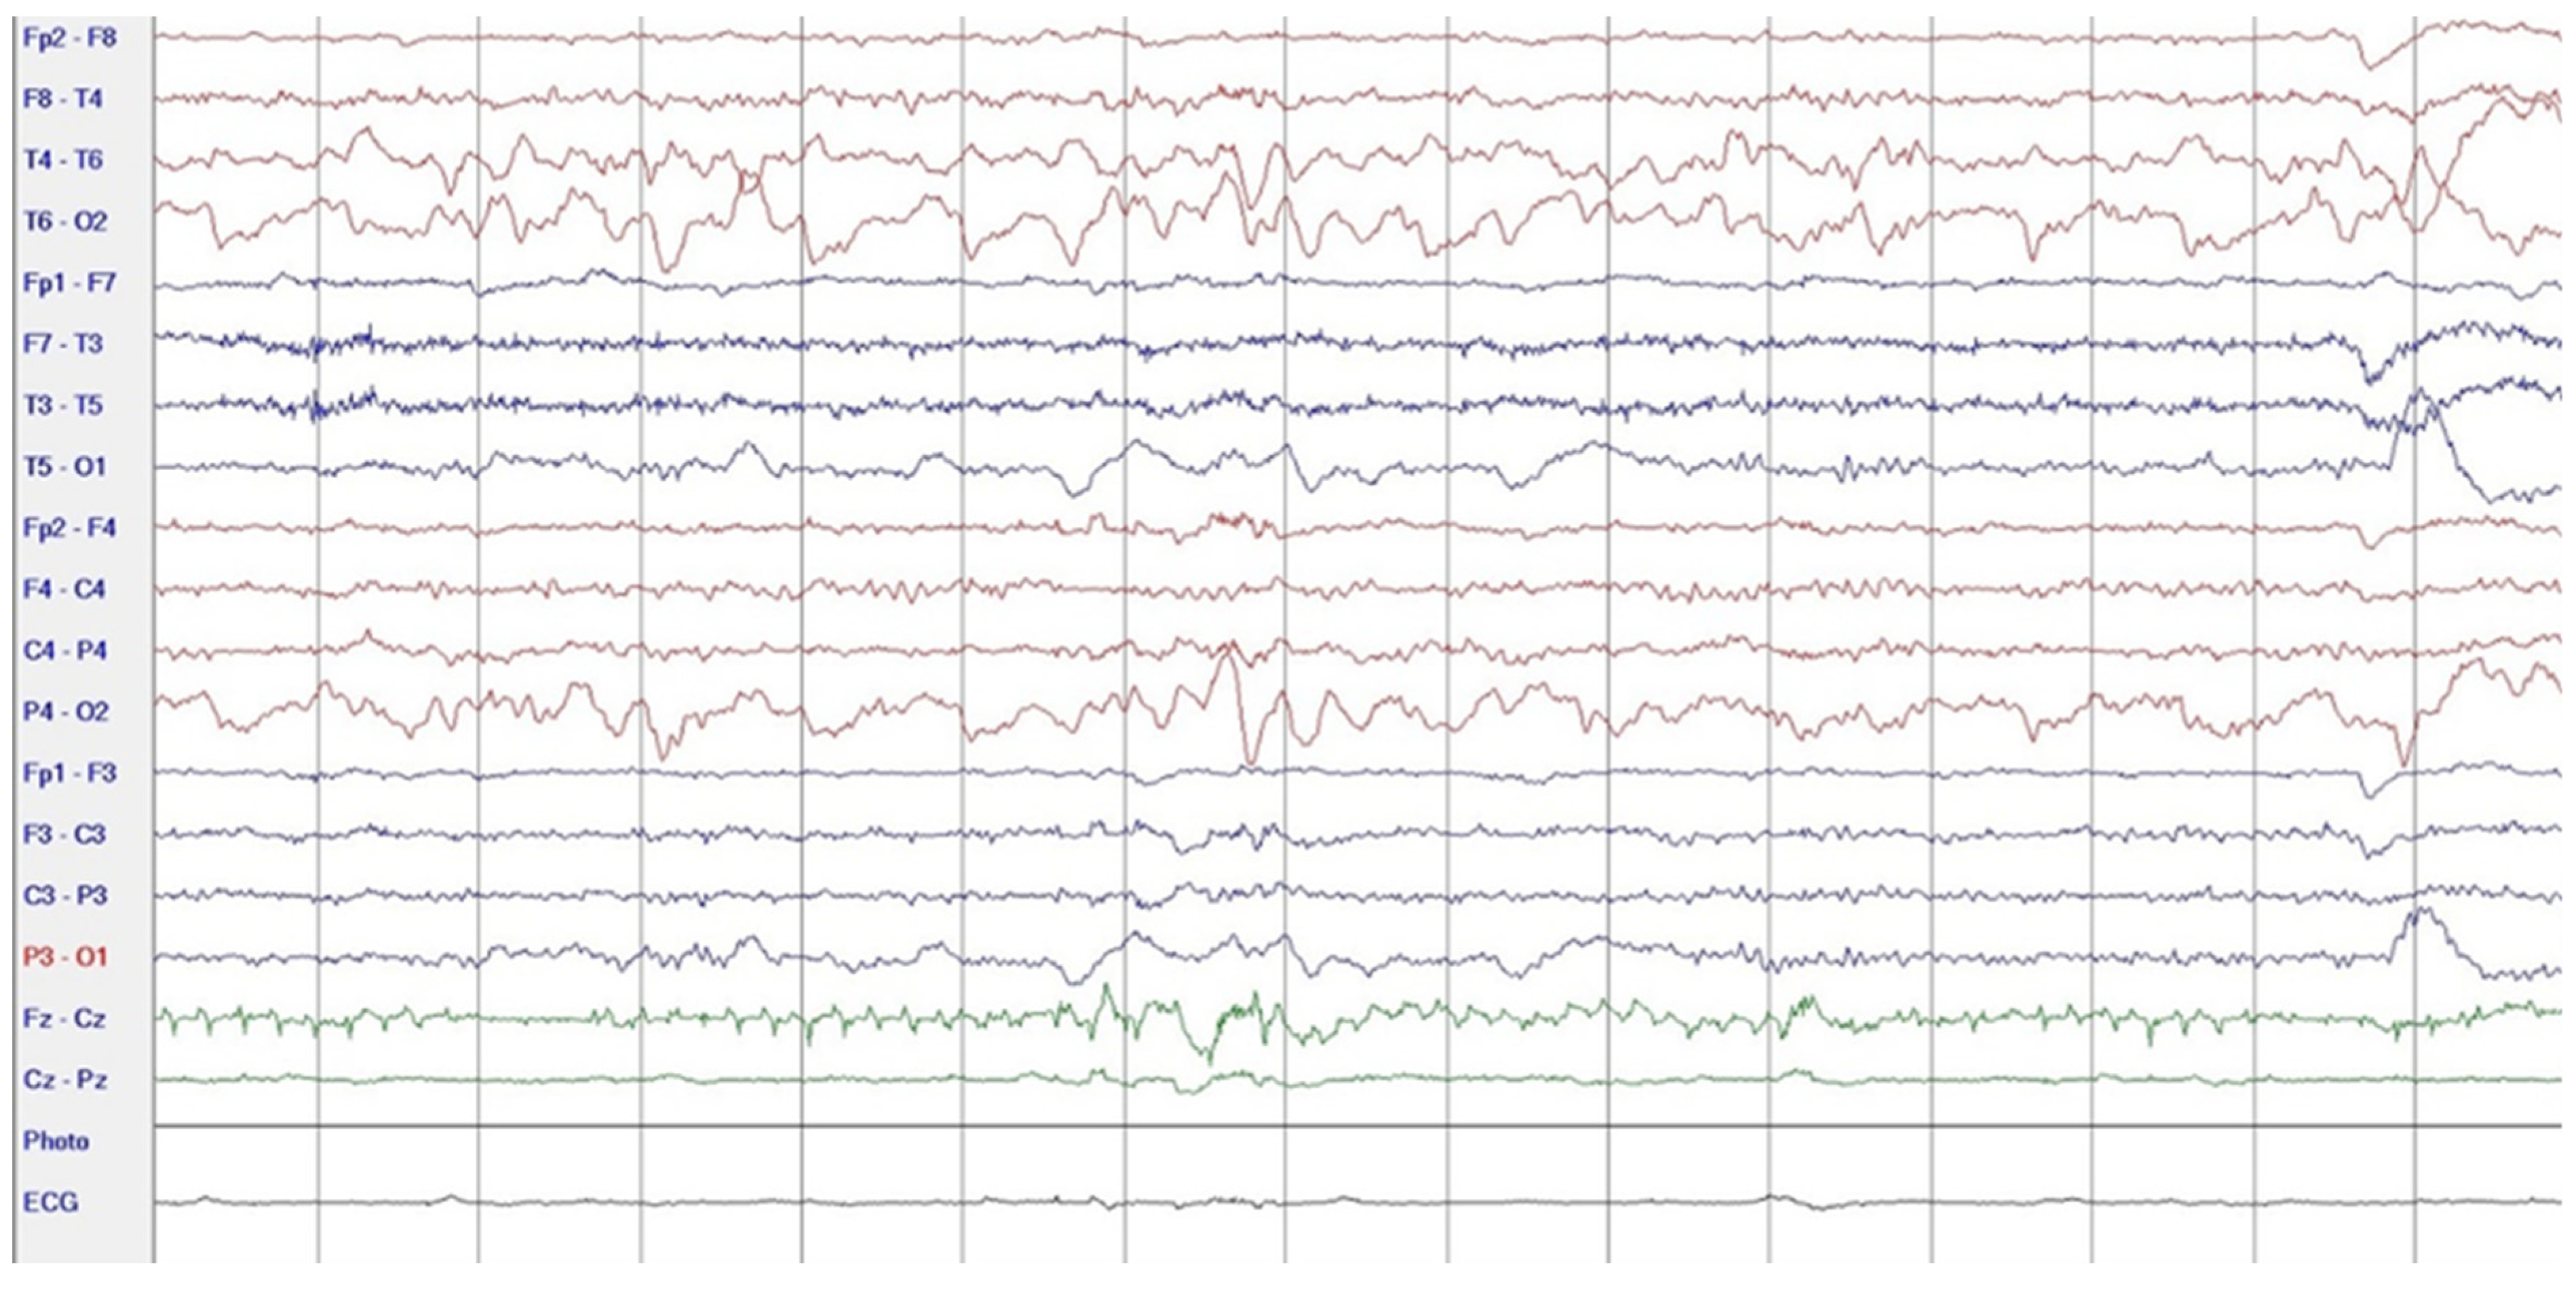

2. Case Report